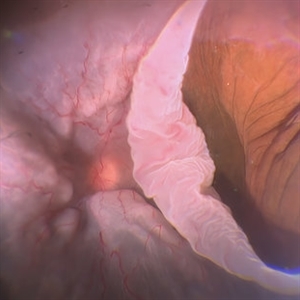

New Choroidal Melanoma with Exudative Detachment

New Choroidal Melanoma with Exudative Detachment

Oct 16 2024 by Virginia Gebhart

56 year old male with a large pigmented tumor with an exudative detachment inferior and shallow fluid through the macula. Pt states they have been having symptoms for over a year. Scheduled for brachytherapy.

Photographer: Virginia Gebhart, Retina Consultants of Carolina

Imaging device: Optos California

Condition/keywords: Choroidal melanoma, exudative detachment, melanoma